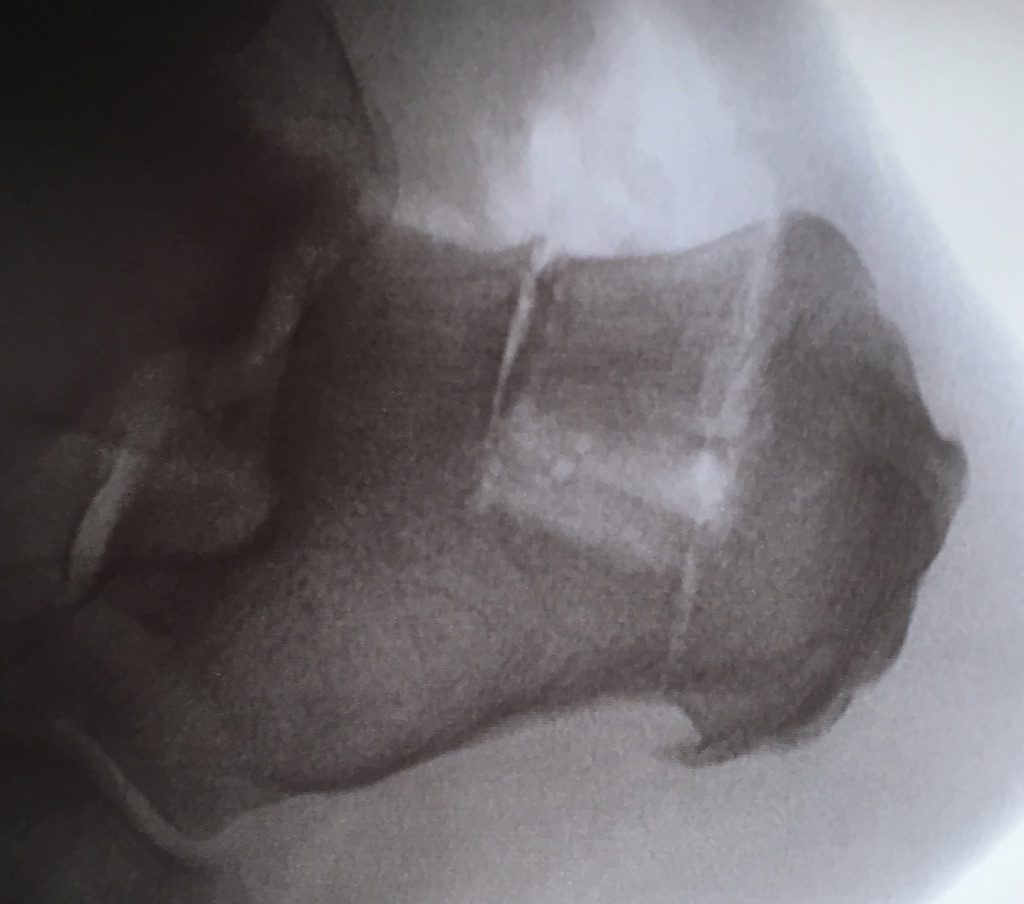

The proximal tibia is another excellent source for cortical and cancellous bone grafts. Unlike marrow from the iliac crest, the marrow of the distal tibia contains quiescent fat, offering no osteogenic properties. Many surgeons favor the proximal tibia over the distal tibia for graft harvest because there is a more sufficient volume of graft available.5

The tibial tuberosity is also a source of cancellous bone when one accesses it by a periosteal-cortical flap. The surgeon must take care to avoid the anterior tibial recurrent and lateral inferior genicular arteries supplying this area.12 The anterior medial tibia is best utilized for its cortical bone, where many surgeons prefer to harvest a cortical-cancellous “window.” When obesity poses a contraindication to iliac crest harvest, the proximal tibia is a viable option because there tends to be a lesser amount of fat stored over the anterior medial tibia. One may harvest 25 cm3 to 40 cm3 from this aspect of the tibia without complication.5

In general, the harvest of graft from the proximal tibia is a very safe procedure. Complication rates range between 1.3 and 2.6 percent.13 Geidemann and team showed zero incidence of serious complications such as infection or fracture in 155 patients.14 Minor post-operative complications include hematoma or incision dysesthesias that will likely resolve within three months post-surgery.15